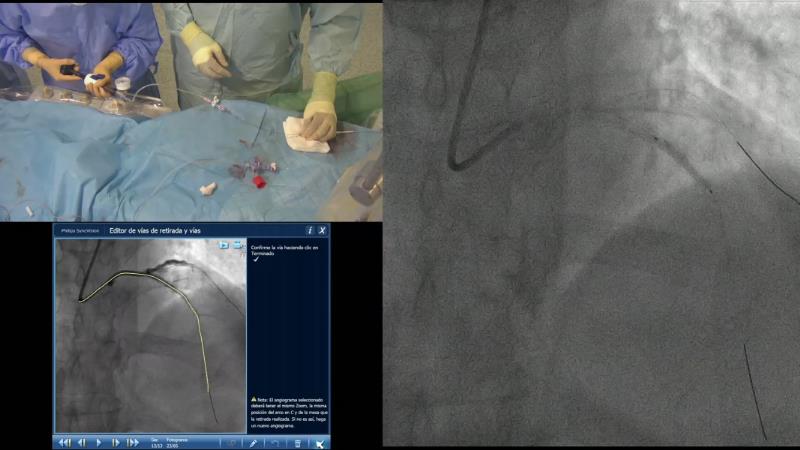

- To learn how physiology pullbacks and angiography co-registration can help to define the patterns of atherosclerotic disease and guide treatment strategy

- To understand how to optimise PCI using physiology

- To learn key tips and tricks to obtain accurate physiological measurements